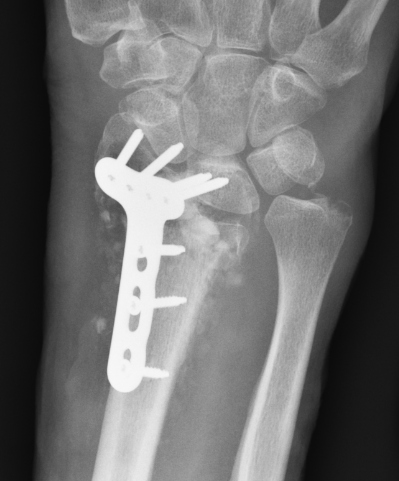

Malunion

www.boneschool.com/distal-radius-fracture-malunion